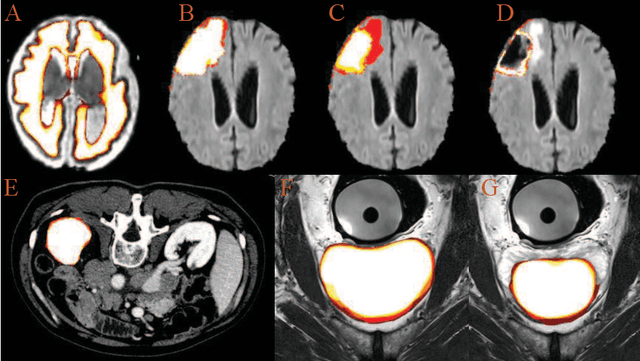

Abstract:Accurate medical image segmentation is crucial for diagnosis and analysis. However, the models without calibrated uncertainty estimates might lead to errors in downstream analysis and exhibit low levels of robustness. Estimating the uncertainty in the measurement is vital to making definite, informed conclusions. Especially, it is difficult to make accurate predictions on ambiguous areas and focus boundaries for both models and radiologists, even harder to reach a consensus with multiple annotations. In this work, the uncertainty under these areas is studied, which introduces significant information with anatomical structure and is as important as segmentation performance. We exploit the medical image segmentation uncertainty quantification by measuring segmentation performance with multiple annotations in a supervised learning manner and propose a U-Net based architecture with multiple decoders, where the image representation is encoded with the same encoder, and segmentation referring to each annotation is estimated with multiple decoders. Nevertheless, a cross-loss function is proposed for bridging the gap between different branches. The proposed architecture is trained in an end-to-end manner and able to improve predictive uncertainty estimates. The model achieves comparable performance with fewer parameters to the integrated training model that ranked the runner-up in the MICCAI-QUBIQ 2020 challenge.